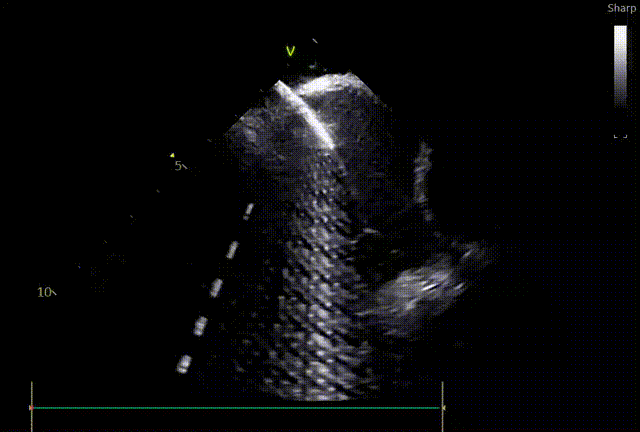

“超声下监测放电过程中,没有看到任何气泡产生。”

不仅中国专家反馈很好,同时FARAPULSE的安全性更是得到数据的验证,超过1.7万例真实性世界研究MANIFEST-17K中,食道瘘,肺静脉狭窄,永久性膈神经损伤均为0%1。手术过程中临床医生以往需要担心的问题得到解决,手术过程更加安心,也为患者带来更加安全的手术体验。

脉冲消融技术的“组织选择性”原理,避免对心肌毗邻组织的损伤